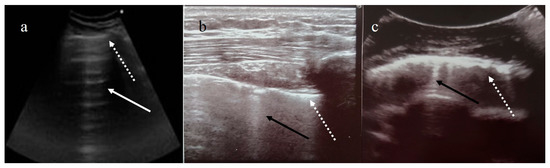

- Sperandeo, M.; Rotondo, A.; Guglielmi, G.; Catalano, D.; Feragalli, B.; Trovato, G.M. Transthoracic ultrasound in the as-sessment of pleural and pulmonary diseases: Use and limitations. Radiol. Med. 2014, 119, 729–740. [Google Scholar] [CrossRef]

- Sperandeo, M.; Varriale, A.; Bianco, M.; Piattelli, M.; Bizzarri, M.; Ghittoni, G.; Copetti, M.; Vendemiale, G.; Sperandeo, G. Characterization of the normal pulmonary surface and pneumonectomy space by reflected ultrasound. J. Ultrasound 2011, 14, 22–27. [Google Scholar] [CrossRef] [Green Version]

- Tinti, M.G.; Rea, G.; Frongillo, E.; Saponara, A.; Sperandeo, M. The pathologic patterns detectable by transthoracic ultraso-nography are only the pleural and subpleural ones and are not specific: Why compare them with high-resolution computed tomography? J. Ultrasound Med. 2018, 37, 1847–1848. [Google Scholar] [CrossRef] [PubMed]

- Quarato, C.M.I.; Venuti, M.; Lacedonia, D.; Simeone, A.; Dimitri, L.M.C.; Rea, G.; Ferragalli, B.; Sperandeo, M. The Role of Transthoracic Ultrasound in the novel Coronavirus Disease (COVID-19): A Reappraisal. Information and Disinformation: Is There Still Place for a Scientific Debate? Front. Med. 2020, 7, 271. [Google Scholar] [CrossRef] [PubMed]

- Monteiro, R.A.A.; BIAS—Brazilian Image Autopsy Study Group; De Oliveira, E.P.; Saldiva, P.H.N.; Dolhnikoff, M.; Duarte-Neto, A.N. Histological–ultrasonographical correlation of pulmonary involvement in severe COVID-19. Intensiv. Care Med. 2020, 46, 1766–1768. [Google Scholar] [CrossRef]